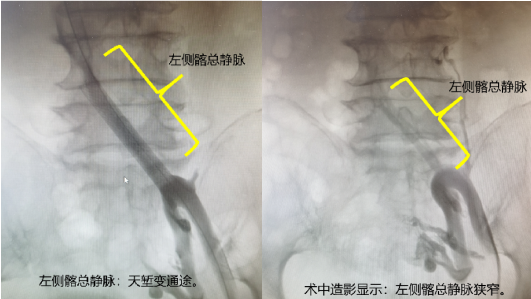

通常来说,针对此次治疗需要进行两台手术:先在DAS下行髂静脉成形术,以缓解压迫症状,再在手术室进行曲张静脉治疗。我科对该患者病情综合讨论后,决定采取复合手术,在同一次手术中解决李阿婆的两个血管问题。手术由张喜成主任和黄献琛副主任共同为患者施行。采用神经阻滞麻醉,在很小的切口下暴露出大隐静脉,通过这个入路,对髂静脉进行血管扩张,植入支架以后髂静脉随即恢复通畅,最后向下采用微创激光治疗的方法处理下肢的曲张静脉。手术在导管室老师的配合下进行顺利。